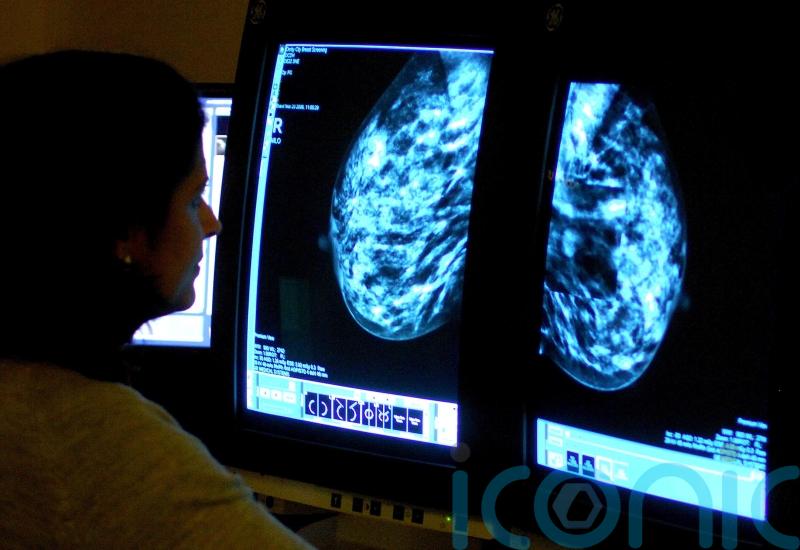

Breast cancer screenings uptake ‘shockingly low’, health minister tells MPs

The uptake of breast cancer screenings is “shockingly low”, a health minister has told the Commons, as she urged women to come forward.

Karin Smyth also told MPs the use of artificial intelligence will help to ensure women receive faster treatment for breast cancer.

Ms Smyth replied: “The screening access uptake is shockingly low across the country right now, and that has to form a key part of what we need to try and do to make sure that women come forward for that screening test.

“The AI work will support that faster response time, so that we can get women treated more quickly and absolutely forms part of what we need to do in the coming years.”